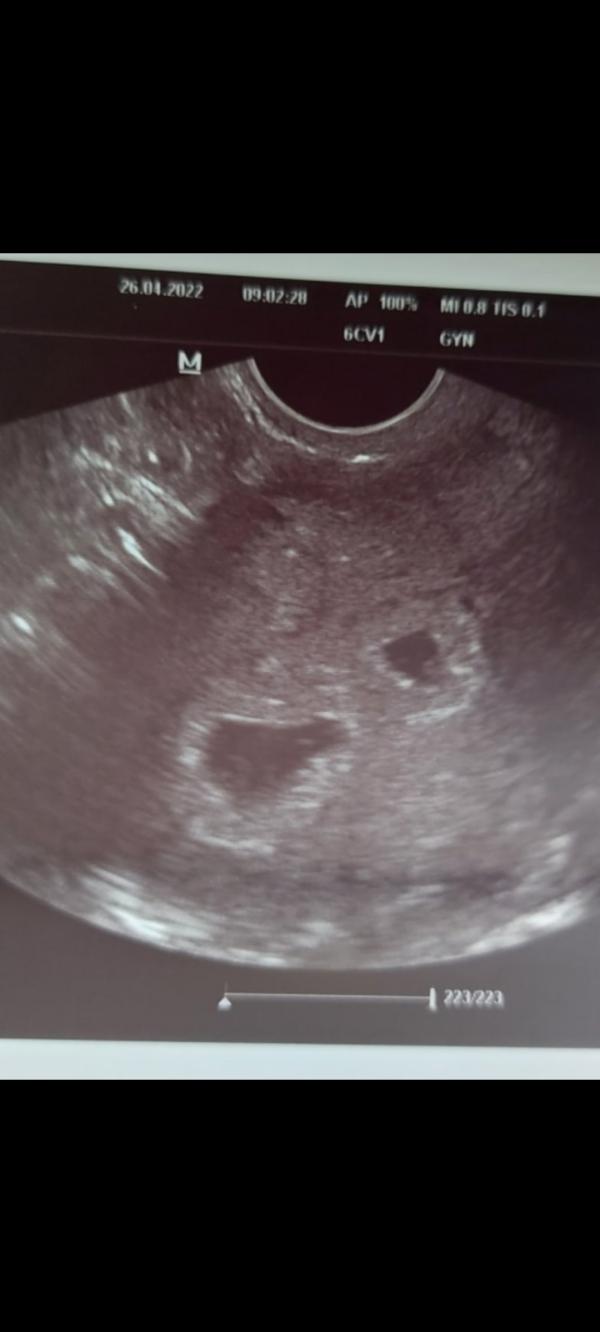

Сегодня ходила на узи🥳🥳🥳

Крохи на месте 🤗 и сердечки их 💞💗💗💗

Я ходила в 5 акушерских, только плодное увидели 7мм и желтое тело. А в 6.5 уже был эмбрион 7.5мм и сердцебиение со звуком, желточный, и пя 19.5мм.